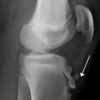

Consider the benefit of arthroscopy for addressing intraarticular pathology at the time initial surgical repair of high-grade ankle fracture is performed. Ankle fractures are a common orthopedic injury. Although surgical repair often yields good results, many cases are nonetheless associated with poor clinical outcome after repair.

By Kevin Burke, DPM and Jonathan Hook, DPM